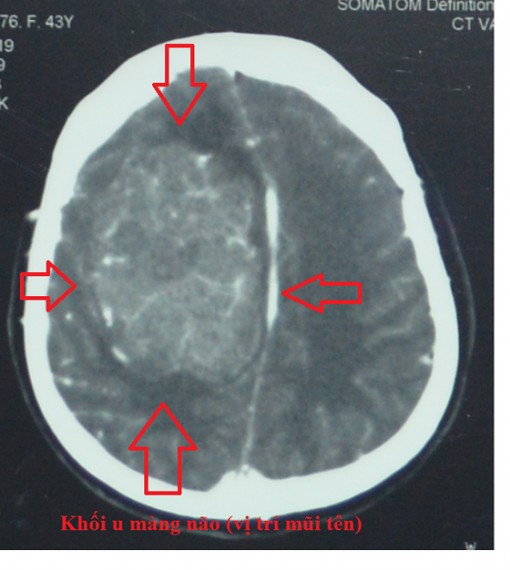

Chiều 9-4, Bệnh viện đa khoa Trung ương Cần Thơ cho biết, vừa phẫu thuật thành công một bệnh nhân bị khối u màng não lớn.